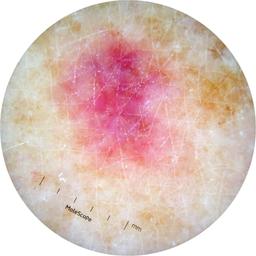

ISIC_2631400

MEL-SELF Trial, https://www.sydney.edu.au/medicine-health/our-research/research-centres/melself-project.html

Clinical

Field Value

acquisition_day 146

age_approx 70

anatom_site_1 Lower extremity

anatom_site_general lower extremity

concomitant_biopsy False

diagnosis_1 Benign

diagnosis_confirm_type single image expert consensus

family_hx_mm True

fitzpatrick_skin_type I

image_manipulation instrument only

image_type dermoscopic

lesion_id IL_2672529

patient_id IP_8223109

personal_hx_mm True

sex female